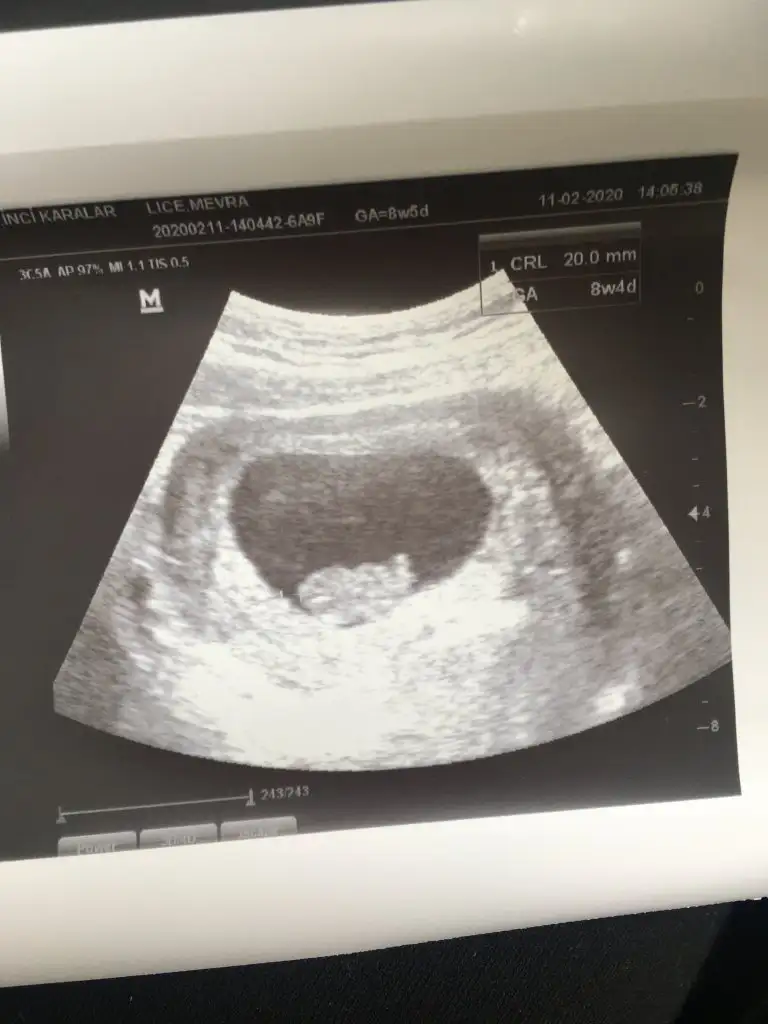

Bebeği gördük bayagi büyümüş arkası bize dönüktü ama 😁 bugun 8+2 yim ama ultrasonda 9+1 gozuktu..sıkıntılı bi durum deildir dimi ileriden gitmesi kızlar..